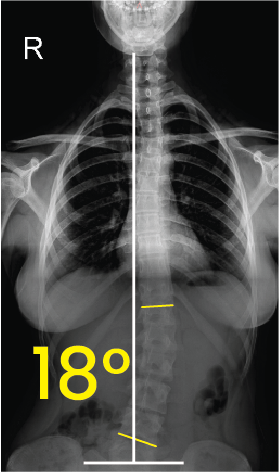

Torakal omurgada sağa doğru 18 derece eğriliği gösteren röntgen görüntüsü.Toraks röntgeninde orta çizgiye göre 11 derece eğimli omurga görünümü.